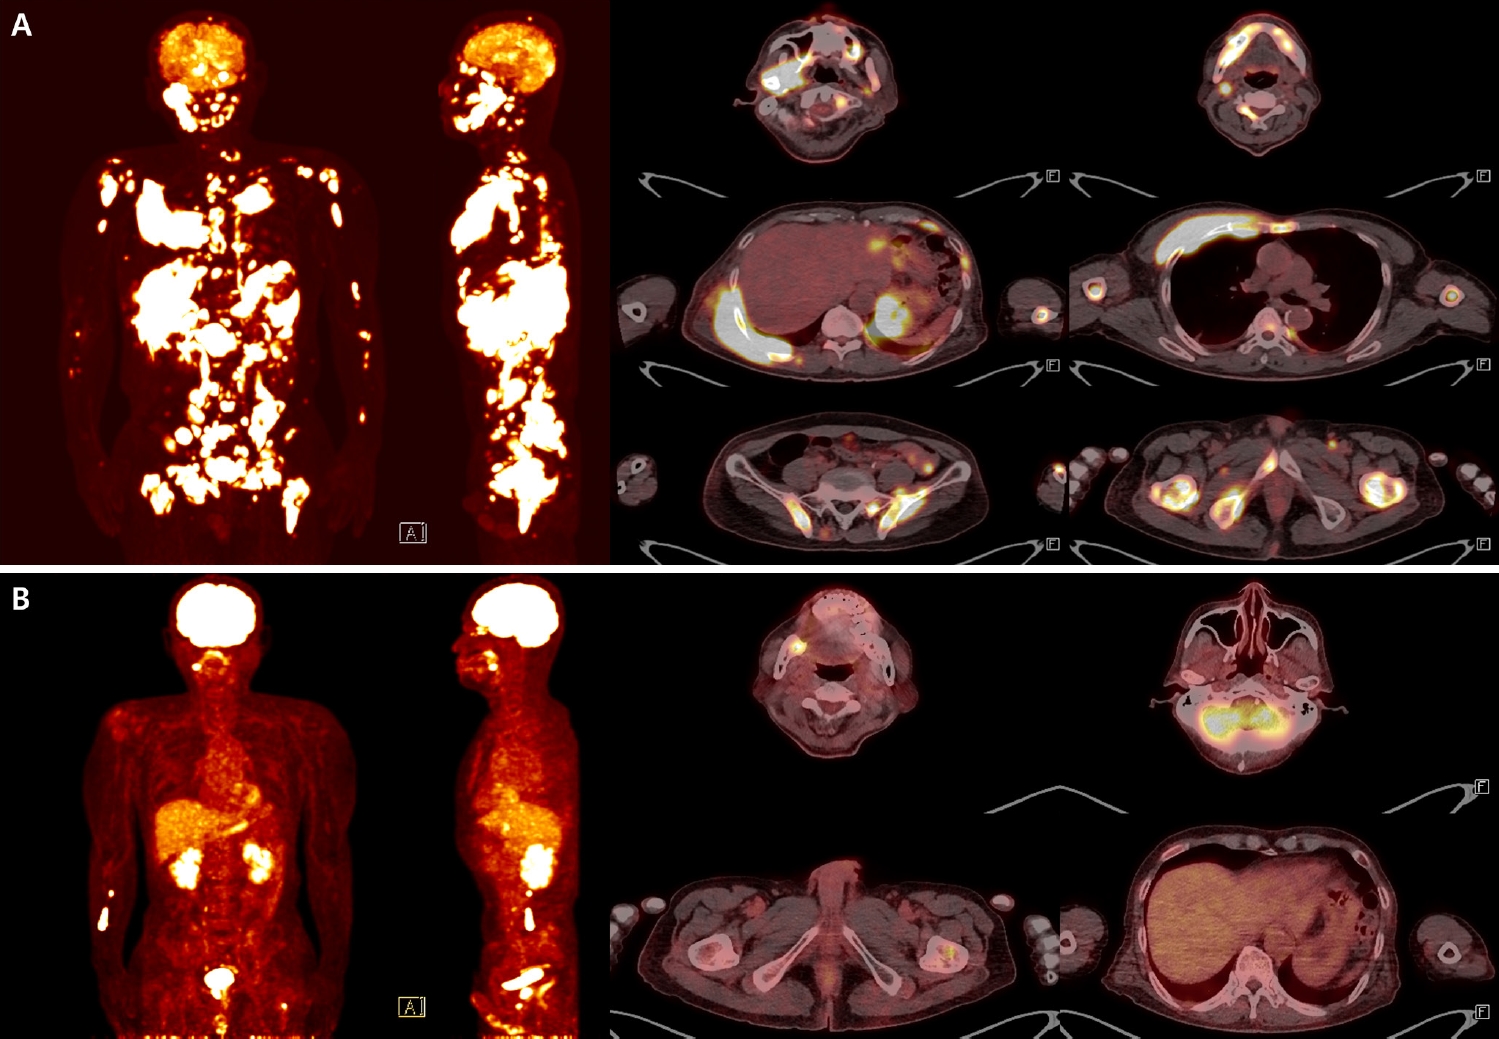

Subsequent systemic work-up revealed widespread disease. Fluorodeoxyglucose positron emission tomography (FDG-PET) demonstrated probable lymphoma involvement of lymph nodes above and below the diaphragm, bones, nasopharynx, tonsil, stomach, subcutaneous tissue and muscles, and lung (Fig. 4A). Cerebrospinal fluid cytospin was positive for malignant lymphoid cells, confirming central nervous system dissemination. In addition, orbit and head CT revealed a suspicious expansile soft tissue lesion in the right ethmoid sinus, together with mild bilateral maxillary sinus mucosal thickening.

Collectively, these findings were diagnostic of BL. Systemic staging with FDG-PET, cerebrospinal fluid cytology, and CT imaging revealed disseminated nodal and extranodal involvement including the central nervous system, corresponding to stage IV disease by Lugano classification. Given the widespread disease and central nervous system involvement, the therapeutic approach was palliative rather than curative. The patient presented with B symptoms, including weight loss and febrile sense, and was initiated on systemic chemotherapy with R-EPOCH (rituximab, etoposide, prednisone, vincristine, cyclophosphamide, doxorubicin). Intrathecal methotrexate (IT-MTX) was administered for central nervous system prophylaxis and treatment, and he is currently undergoing the fourth cycle of R-EPOCH with IT-MTX. Thus far, the patient has tolerated therapy well without treatment-related complications, and follow-up imaging demonstrated marked improvement of the lesions (Fig. 4B).

Fig. 4.

Fluorodeoxyglucose positron emission tomography–computed tomography (FDG-PET/CT) images at diagnosis and after chemotherapy. Baseline FDG-PET/CT at diagnosis demonstrates disseminated hypermetabolic lesions involving multiple nodal stations (bilateral neck, axilla, mediastinum, abdomen, and pelvis) and extensive extranodal sites, including the skull, mandible, spine, long bones, clavicle, sternum, ribs, scapula, pelvis, lung, stomach, gallbladder, pancreas, nasopharynx, tonsil, and widespread subcutaneous and muscular tissues, consistent with advanced-stage Burkitt lymphoma (A). Follow-up FDG-PET/CT after the fourth cycle of chemotherapy shows a markedly improved state. Only focal residual uptake persists in the right mandible and left proximal femur (B).

Fig. 4. Fluorodeoxyglucose positron emission tomography–computed tomography (FDG-PET/CT) images at diagnosis and after chemotherapy. Baseline FDG-PET/CT at diagnosis demonstrates disseminated hypermetabolic lesions involving multiple nodal stations (bilateral neck, axilla, mediastinum, abdomen, and pelvis) and extensive extranodal sites, including the skull, mandible, spine, long bones, clavicle, sternum, ribs, scapula, pelvis, lung, stomach, gallbladder, pancreas, nasopharynx, tonsil, and widespread subcutaneous and muscular tissues, consistent with advanced-stage Burkitt lymphoma (A). Follow-up FDG-PET/CT after the fourth cycle of chemotherapy shows a markedly improved state. Only focal residual uptake persists in the right mandible and left proximal femur (B).